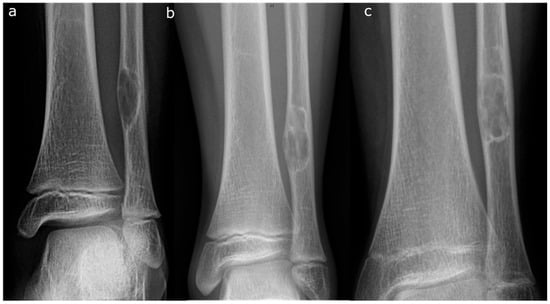

- Pac-Man Sign—Proliferation of bone anterior and posterior to the syndesmosis results in a shape that resembles the video game character “Pac-Man”. This sign was found to be highly specific (95%) but not very sensitive (47%) for predicting pathologic fracture (Figure 3).

- Computed Tomography (CT): CT can be useful for evaluating the degree of cortical thinning, which is important when assessing fracture risk [24]. CT is superior for delineating the precise cortical integrity. It allows for quantitative measurement of the cross-sectional area occupied by the lesion, which is a key factor in biomechanical models predicting fracture risk. The signs described above can also be visualized on a CT scan. Figure 3 demonstrates a “Pac-Man Sign” on CT of a 13-year-old boy who had a fracture through an NOF.

- Curettage and Bone Grafting: This is by far the most performed procedure. After curettage, the cavity is filled with autograft, allograft, or synthetic bone substitute [32]. While autograft is theoretically biologically superior, the donor site morbidity makes allograft the most used graft choice. In addition, the relatively high success rate and low risk of recurrence make the risks of an additional incision with autograft prohibitive. Synthetic substitutes such as calcium sulfate and calcium phosphate can provide structural support to allow earlier weight bearing. Again, the risks of cementation, in the setting of a benign disease with good operative results, make this a less common choice. Adjuvants are typically not used in the curettage stage for NOFs, as they are in giant cell tumors of bone or aneurysmal bone cysts. NOFs are not locally aggressive, and the use of phenol or argon beam coagulation is not typically indicated to reduce recurrence. Phenol and argon have a risk of local tissue damage, making them uncommonly used in the setting of NOFs. Figure 5 demonstrates pre-, intra-, and post-operative radiographic images of a 17-year-old boy with a large symptomatic distal tibia NOF who underwent a curettage and bone grafting procedure.